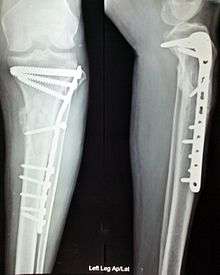

Anterior and lateral view x-rays of fractured left leg with internal fixation